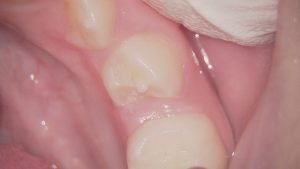

歯の形態異常である中心結節という突起は、小学生くらいの永久歯が生えてきた時期、ご家族の仕上げ磨き時に気づくこともあります。

下の奥歯と前歯の間くらいの小臼歯という歯に生じやすいです。

6歳臼歯の手前の小臼歯生じやすい

厄介なことに、突起の先端まで神経が入り込んでいることが多いです。